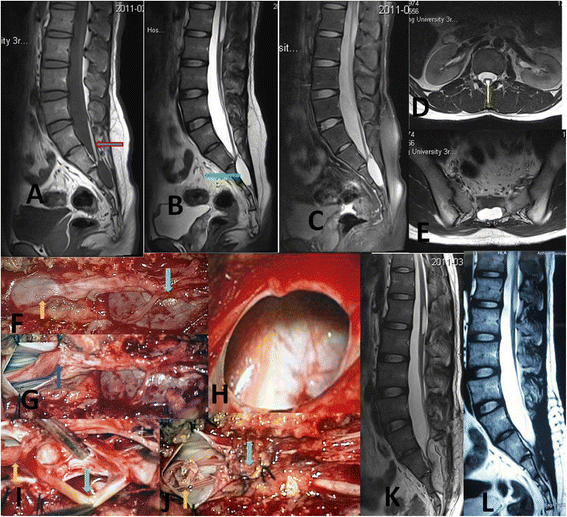

(a) Location of the cyst (*) in the nerve root axilla (T Thecal sac

(a) Location of the cyst (*) in the nerve root axilla (T Thecal sac Back Cyst Nerve Synovial cysts can affect one side of the spine or both, and they can occur at one spinal segment or at multiple levels. These usually occur at the base (bottom part) of your spine. if a synovial cyst is compressing a nerve, it can cause back pain, weakness, or numbness. what are the symptoms of spinal cysts? Depending. Back Cyst Nerve.

From cnjournal.biomedcentral.com

Classification, mechanism and surgical treatments for spinal canal Back Cyst Nerve Depending on the size and location of the cyst, symptoms may be similar to those of spinal stenosis, including:. if a synovial cyst is compressing a nerve, it can cause back pain, weakness, or numbness. Synovial cysts can affect one side of the spine or both, and they can occur at one spinal segment or at multiple levels. Symptoms. Back Cyst Nerve.